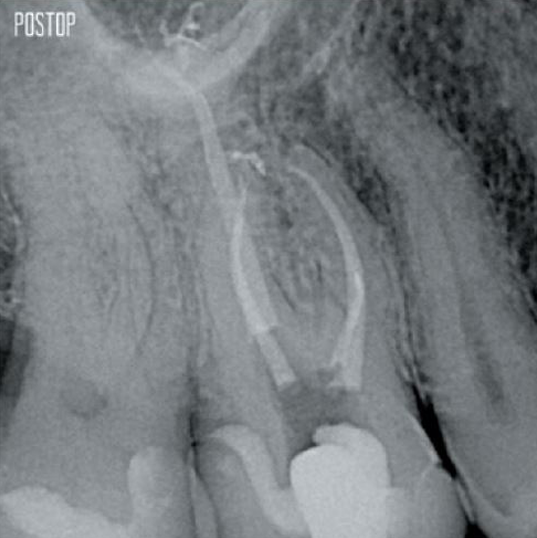

Foto's met dank aan dr. Ahmed Salman

Voor een complete, endodontische ervaring kunnen TruNatomy®-vijlen gecombineerd worden met de volgende producten voor verbeterde desinfectie en specifieke obturatie, die naadloos samenwerken:

Ja, de TruNatomy Conform Fit®Guttapercha-punten zijn ontworpen om perfect aan te sluiten op de voorbereidingen die worden gemaakt met TruNatomy-vijlen en zorgen voor een optimale obturatie.

Dankzij de flexibiliteit van de TruNatomy Irrigatienaald kan deze apicaal in gebogen kanalen van minder dan 12 mm komen.